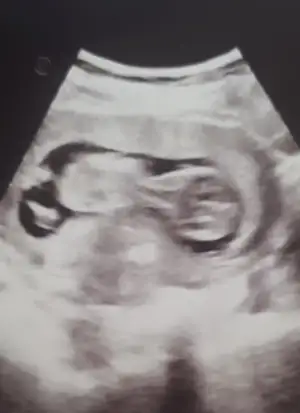

Merhaba hayırlı sabahlar tecrübeli arkadaşlardan cinsiyet tahmini rica edebilirmiyim acaba

• IMG_20210907_164357.webp

IMG_20210907_164357.webp

31,8 KB · Görüntüleme: 94